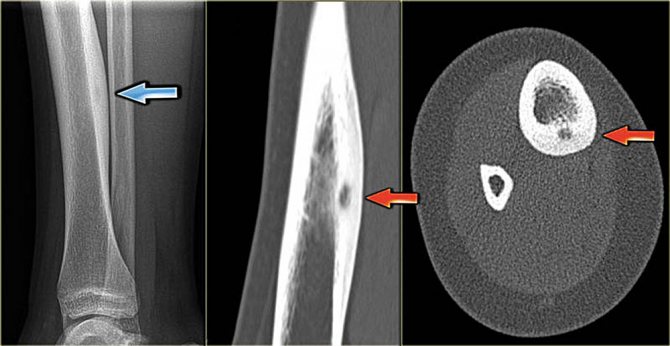

Специалист может назначать пациенту рентгенографию, с помощью которой удается распознать опухоль, а также выявить, где она находится, определить точные размеры. Для уточнения диагноза больному требуется компьютерная томография и биопсия. Биоматериал уплотнения извлекается оперативным вмешательством либо методом пункции.

Методы диагностики

Для проведения качественной диагностики необходимо использовать комбинацию клинических и рентгенологических исследований. Если поставить ошибочный диагноз, цена может оказаться слишком высокой, ведь неправильное лечение способно спровоцировать массу осложнений, особенно когда речь идет об онкологии.

Диагностика может включать такие мероприятия:

- пальпация проблемной области;

- оценка степени функционирования пораженного сустава;

- выполнение рентгеновского снимка (неэффективно при мелких опухолях);

- КТ для более подробной оценки проблемы;

- МРТ позволяет определить точный тип новообразования;

- сцинтиграфия;

- взятие пробы для проведения гистологических анализов.

С помощью томографии удается воссоздать 3D модель проблемного сустава, рассмотреть все его составляющие части и с максимальной точностью определить размеры и плотность остеомы. Это помогает определить наиболее подходящую тактику лечения.